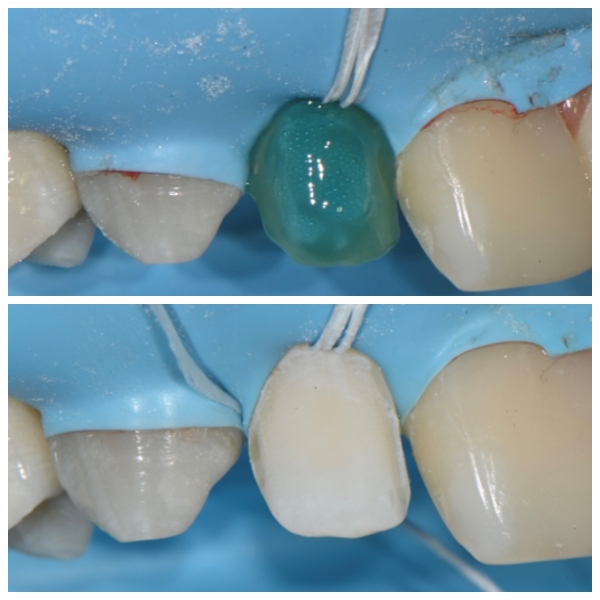

가운데 벌어진 부분은 바이오클리어레진으로 치료를 시행합니다

이 부분은 라미네이트를 하게 되면 삭제가 엄청 많아지게 됩니다

그렇게 되면 너무 불편하고 치아의 수명이 짧아질수 있습니다

그런 이유로 이런경우엔 저희는 바이오클리어레진을 많이 선택하는데요

바이오클리어레진으로 치료하는 과정입니다

좌우의 대칭과 치아의 색상을 맞추어서 치료를 하는 과정이지요

치아의 삭제가 0 즉 제로라는 점에서 굉장히 매력적인 치료방법입니다

하지만 그만큼 시간이 오래 걸리고 상당히 테크닉한 방법이지요

완성이 되어가고 있는 과정입니다 1차 완성

치아의 형태가 거의 만들어지고 있습니다

라미네이트 접착도 러버댐이 시작입니다

라미네이트 접착도 레진과 같이 러버댐이 없으면

절대 오래가지 못합니다 .그리고 깨지기도 쉽지요

이렇게 마취를 하고 하나하나 러버댐을 체결하고 라미네이트를 셋팅해야 합니다

이런 모든 과정이 필수이지요

최종적으로 붙이면서 그리고 안에 있는 접착제를 철저히 제거해줍니다

안쪽에 접착제가 잔존해 있다면 나중에 문제가 될 수 있지요

1차적으로 라미네이트 접착이 완료된 사진입니다.

반대편도 같은 과정을 반복합니다

이렇게 러버댐으로완전히 격리를 시키면서 접착을 해야

안정적으로 라미네이트 접착이 이루어집니다